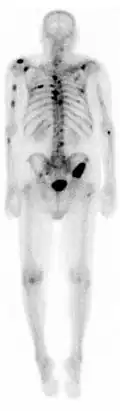

Cintigrafia óssea

Cintigrafia óssea ou gamagrafia óssea é uma técnica de diagnóstico por imagem de medicina nuclear usada para diagnosticar várias condições ósseas, incluindo cancro (primário ou metástase) no osso, osteíte(inflamação do osso), fraturas ou fissuras ósseas (que podem não ser visíveis em imagens de raios X tradicionais) e infecção óssea (como artrite séptica).[1]

A cintigrafia fornece imagens funcionais, permitindo a visualização do metabolismo ósseo ou da remodelação óssea, que técnicas de imagem como tomografia simples e raio X não conseguem. O PET Scan (tomografia por emissão de positrões) também permite imagens funcionais do metabolismo, mas é consideravelmente mais caro.[2]

Injetando 6.3 milisievert (mSv) de Tecnécio 99m as imagens do metabolismo ósseo podem ser obtidas em 2 a 5h depois. Normalmente produz uma imagem anterior e uma posterior, mas pode ser combinado com uma Tomografia computadorizada por emissão de fóton único (SPECT) para maior especificidade.[3]